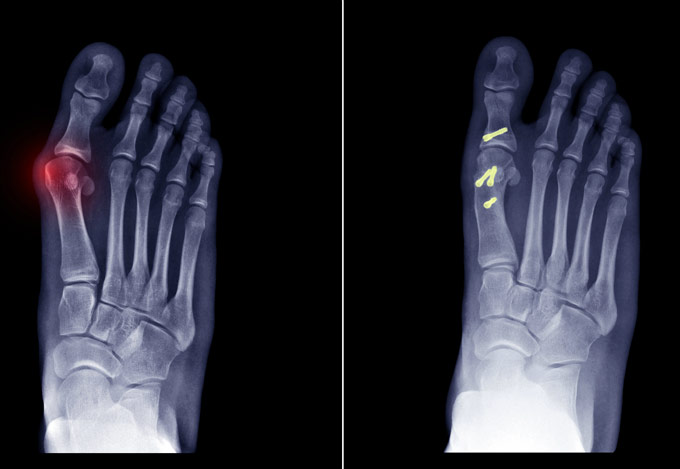

Έχει 5ετή μετεκπαίδευση και εργασία στο Ηνωμένο Βασίλειο ως ειδικός Ορθοπαιδικός Χειρουργός. Έχει εργαστεί στα Ορθοπαιδικά Τμήματα των Νοσοκομείων Southampton University Hospitals NHS Trust, Leeds Teaching Hospitals NHS Trust και στο Northampton General Hospital NHS Trust, με υποεξειδίκευση στη Χειρουργική Ώμου, Γόνατος, Ισχίου, Ποδοκνημικής & Άκρου Ποδός, Ώμου & Αγκώνος και Γενικού Τραύματος Ενηλίκων και Παίδων.